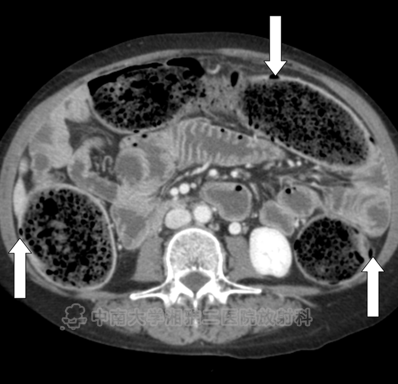

● 在结肠中有明显的粪块残留,在结肠壁(箭头)内存在气体,相关肠壁无增厚或肠系膜脂肪的滞留,与结肠囊样积气一致。

● 在空肠(箭头所示)中有一堆又细又直的褶皱。